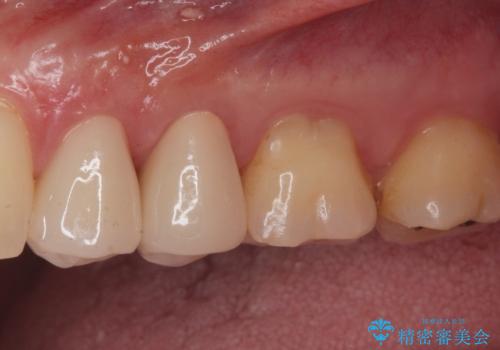

白い被せ物を入れたことにより銀が目立たなくなり

染みることもなくなりました。

ご希望に沿った治療となり大変満足して頂けました。